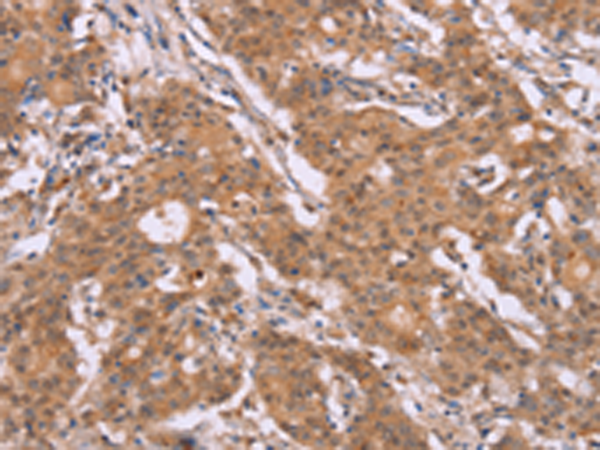

分类: 科研抗体货号: P08182别名: p38; CRKII应用: IHC反应种属: Human, Mouse, Rat

分类: 科研抗体货号: P08183别名: COT应用: WB,IHC反应种属: Human, Mouse, Rat

分类: 科研抗体货号: P08199别名:应用: IHC反应种属: Human

分类: 科研抗体货号: P08181别名: Aeg2; CRS3; SGP28; CRISP-3; dJ442L6.3应用: IHC反应种属: Human

分类: 科研抗体货号: P08198别名: CTX; CP27; CYP27应用: WB,IHC反应种属: Human, Mouse

分类: 科研抗体货号: P08209别名:应用: WB,IHC反应种属: Human

分类: 科研抗体货号: P08197别名: FHI; CPN1; CYP11B; P450C11应用: IHC反应种属: Human

分类: 科研抗体货号: P08208别名:应用: IHC反应种属: Human

分类: 科研抗体货号: P08196别名:应用: IHC反应种属: Human, Mouse

分类: 科研抗体货号: P08207别名: AREI; STF1; STFA应用: WB反应种属: Human, Mouse